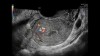

• Voluson Expert 22 real vaxtda yüksək məkan həssaslığına malik görüntülərin əldə olunmasını təmin edən avansert 4D volumetrik görüntüləmə texnologiyasından istifadə edir və bu, klinik diaqnostikanın dəqiqliyini əhəmiyyətli dərəcədə artırır.

• Yüksək keyfiyyətli təsvirlər struktur və funksional dəyişikliklərin daha etibarlı şəkildə qiymətləndirilməsinə şərait yaradır, diaqnostik inam səviyyəsini yüksəldir.

• 3D/4D volumetrik görüntüləmə

• HDlive Studio+ (avansert render texnologiyası)